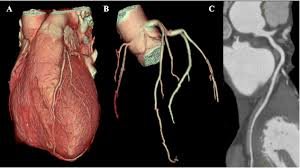

Le coroscanner, en tant qu’outil d’imagerie non invasive, a transformé le paysage de la cardiologie moderne.

Principes et déroulement de l’examen Principe : Le coroscanner utilise des rayons X pour créer des images en coupes fines du cœur et de ses artères. L’injection d’un produit de contraste iodé permet de rendre les artères visibles. Fonctionnement : Un appareil de scanner avec un anneau émet les rayons X....